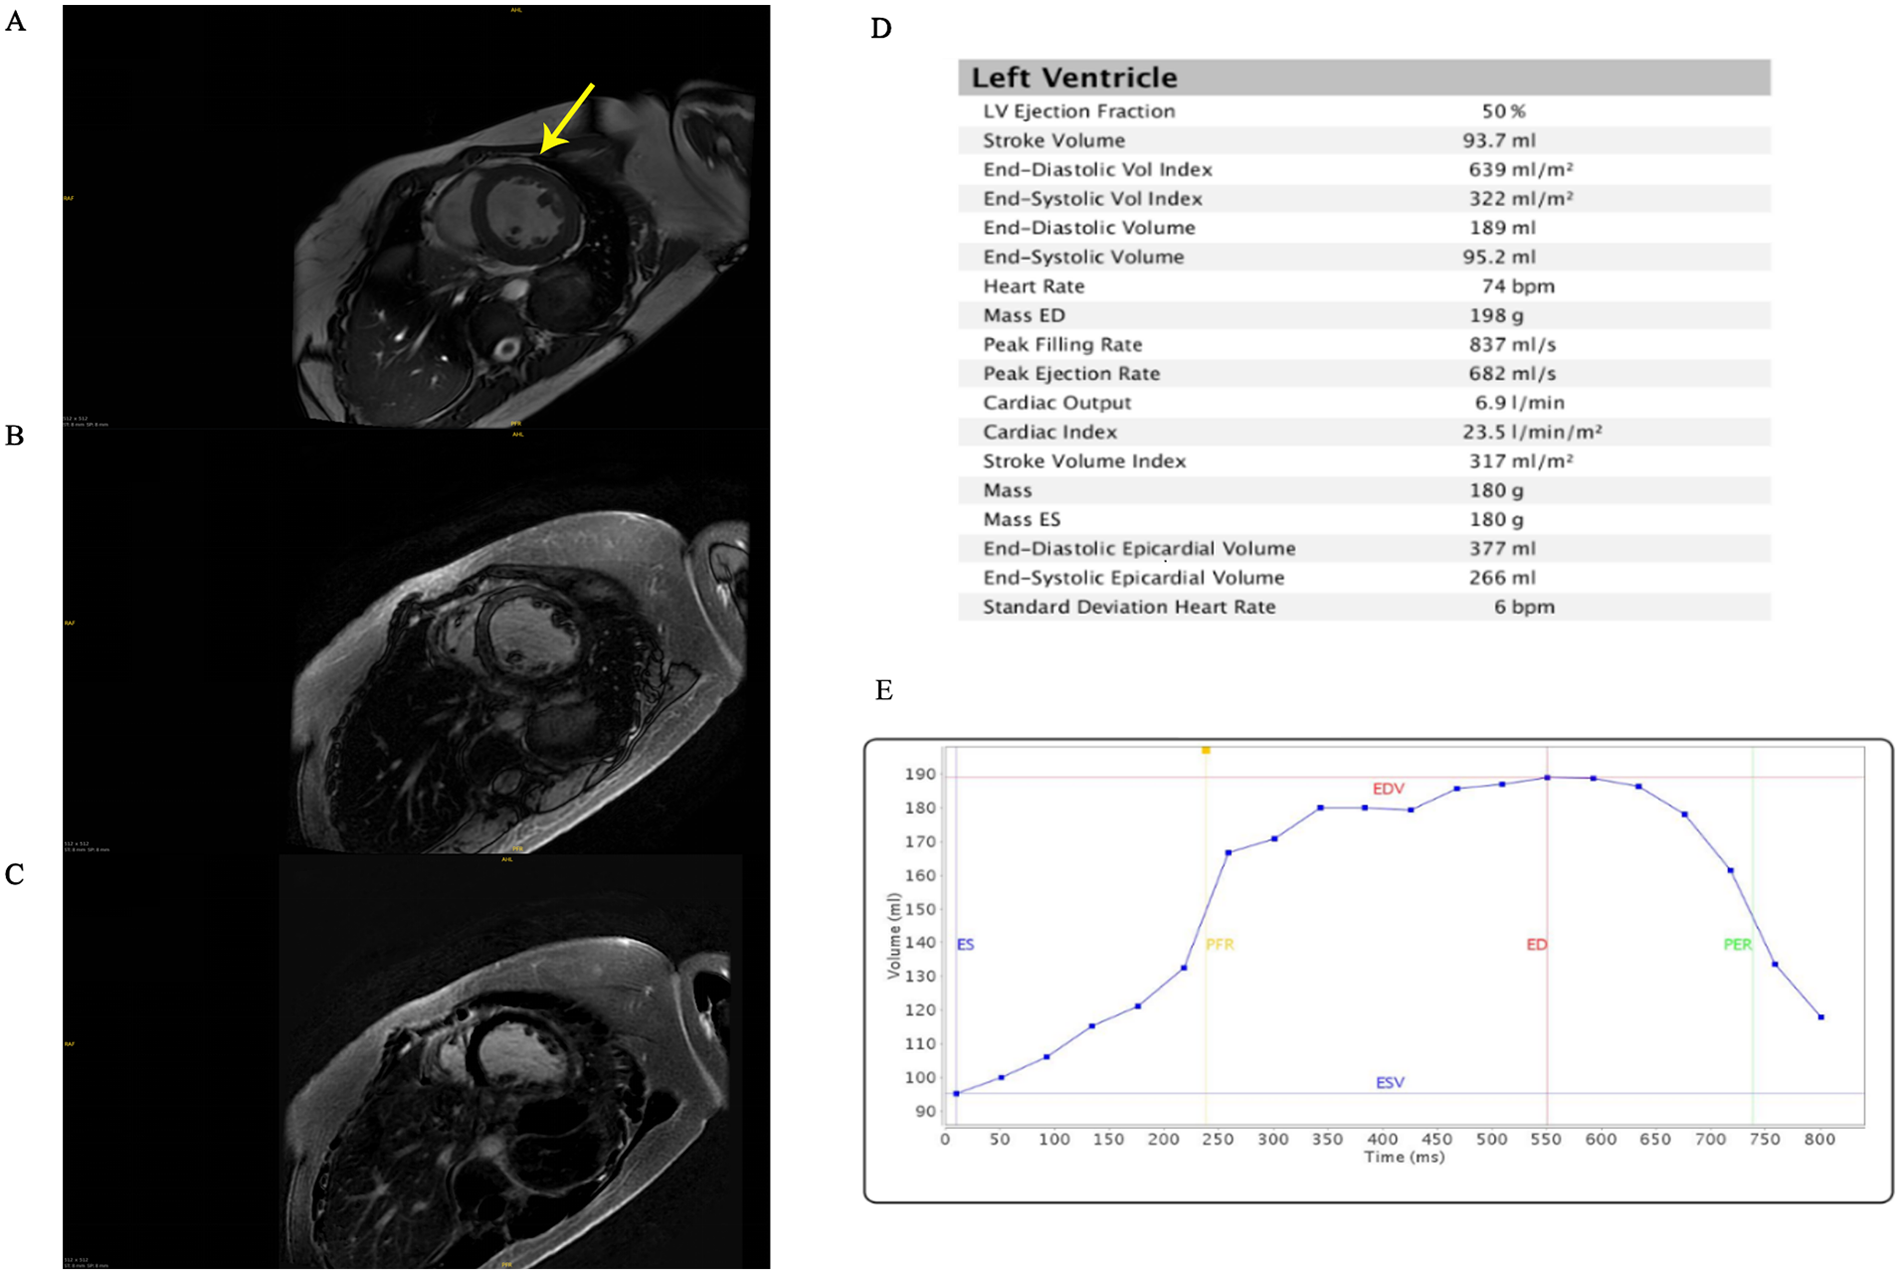

Echocardiography demonstrated a dilated left ventricle (left ventricular end diastolic diameter: 64 mm), left ventricular non-compaction, severe mitral regurgitation, mildly elevated pulmonary arterial systolic pressure (37 mmHg), and severely reduced left ventricular ejection fraction (34%). Cardiac magnetic resonance imaging confirmed left ventricular dilatation and prominent apical trabeculation (Figure 1). However, the findings did not meet the criteria for left ventricular non-compaction (LVNC) (8). Electrocardiography (ECG) showed no signs of myocardial ischemia.

Figure 1

Cardiac magnetic resonance imaging. (A) T1 mapping. The arrow points to the presence of abundant muscle trabeculae in the left ventricle. (B) Late gadolinium enhancement. (C) T2 fat saturation. (D) Left ventricular parameters. (E) Time-volume function. ES, end-systolic; ED, end-diastolic; EDV, end-diastolic volume; ESV, end-systolic volume; PFR, peak filling rate; PER, peak rejection rate.